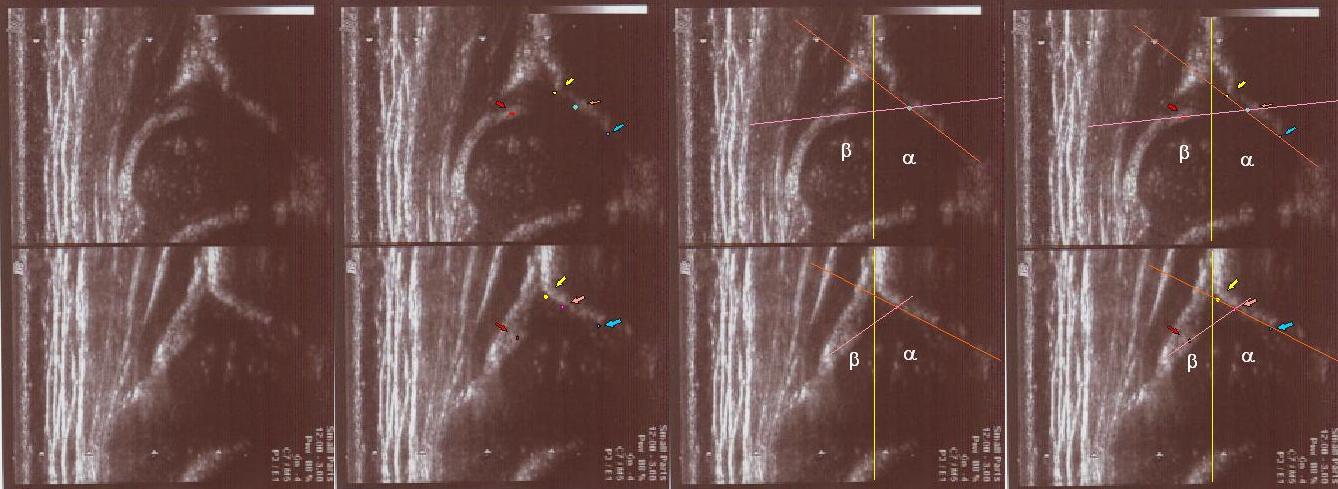

type I (abow) 6 weeks the bony roof is good

the bony rim blunt

the cartilage roof cover the head;

the arrows show labrum (red) ;

the bony rim (yellow);

the lower iliac margin (blue) ,

the bony roof line (blue) is extends tangential to the lower iliac margin and tangent to the bony rim

the cartilage roof line(green) is drown tangential to the bony rim and through the middle point of the labrum echo ;

asymmetry in the loose joint capsule ,family DDH( when it occurs ask always about it)

the baseline (yellow) is drown parallel to ilium echo through the point of the junction of the perichondrium,the periosseum and ilium.

type IIa ( below ) 4 weeks the bony roof is adequate

the bony rim rounded

the bony roof line (green) is extends tangential to the lower iliac margin and tangent to the bony rim

the cartilage roof(blue) is drown tangential to the bony rim and through the middle point of the labrum

type II/D(up) 4 weeks the bony roof severely deficient ,

the bony rim flattened

the cartilage roof dispalced;

the bony roof line (green) is extends tangential to the lower iliac margin and tangential to the bony rim

the cartilage roof line(blue) is drown tangential to the bony rim and through the middle point of the labrum

type IIc (up) 6 weeks the bony roof severely deficient ,

the cartilage roof still covers ;

the bone roof line (red)

the cartilage roof line(pink)

the baseline (yellow)

type D(up) 1 weeks the bony roof severely deficient ,

the bony roof line (green)

the cartilage roof line(blue)